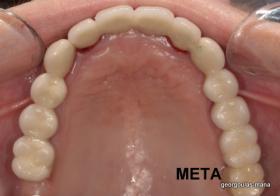

ΟΛΙΚΗ ΑΠΟΚΑΤΑΣΤΑΣΗ ΑΝΩ Κ ΚΑΤΩ ΓΝΑΘΟΥ ΜΕ ΕΜΦΥΤΕΥΜΑΤΑ, ΑΜΕΣΗ ΦΟΡΤΙΣΗ Κ ΑΝΟΙΚΤΗ ΑΝΥΨΩΣΗ ΙΓΜΟΡΕΙΟΥ

Η ασθενής αυτή είχε παλιές ακίνητες αποκαταστάσεις (γέφυρες) στην άνω γνάθο  κ μια κινητή προσθετική αποκατάσταση (μερική οδοντοστοιχία-"μασελάκι") στην κάτω γνάθο. Ήταν δυσαρεστημένη τόσο με την εμφάνιση όσο και με τη λειτουργία των δοντιών της καθώς παραπονιόταν ότι  είχαν εντονη κινητικότητα ενώ και οι προσθετικές τους εργασιές δεν ήταν σταθερές. Η πρόγνωση των δοντιών κρίθηκε φτωχή με αποτέλεσμα να μην είναι δυνατή η συμμετοχή τους σε μια νεα προσθετική αποκατάσταση με μακροχρόνια διάρκεια. Η ασθενής επιθυμούσε οι νέες αποκαταστάσεις να είναι σταθερές και ακίνητες.  Για το λόγο αυτό αποφασίστηκε η ολική αποκατάσταση της άνω κ κάτω γνάθου με ακίνητες επιεμφυτευματικές εργασίες. Στην αριστερή πλευρά της άνω γνάθου, λόγω μη επαρκούς οστού για την τοποθέτηση εμφυτευμάτων προηγήθηκε επέμβαση ανοιχτής  ανύψωσης ιγμορείου άντρου με τη χρήση πιεζοχειρουργικού μηχανήματος ώστε να δημιουργηθεί το κατάλληλο οστικό υπόστρωμα. Ακολούθησε σε επόμενο χειρουργείο η εξαγωγή των υπάρχοντων δοντιών κ η άμεση τοποθέτηση εμφυτεύματων (άμεση εμφύτευση) κ δύο μέρες μετά η τοποθέτηση προσωρινής εργασίας επί των εμφυτευμάτων (άμεση φόρτιση) με αποτέλεσμα η ασθενής να μη μείνει καθόλου χωρίς δόντια κ να είναι καλυμένη αισθητικά όσο καιρό διήρκησε η εργασία